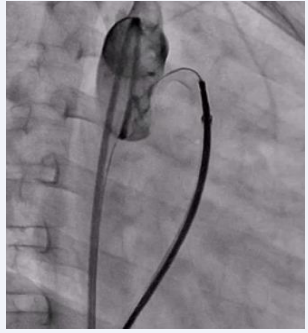

A 7-year-old male child, born to a diabetic mother from a non-consanguineous marriage, presented with a history of respiratory distress immediately after birth, for which he received NICU care during the neonatal period. The patient never underwent a screening echocardiogram during infancy. During a consultation for exertional breathlessness while playing, he was evaluated and underwent screening echocardiography. The echocardiogram (Figure 1),

Transthoracic echocardiogram showing PDA with left-to- right shunt.

Figure 1: Transthoracic echocardiogram showing PDA with left-to- right shunt.

suggested a small 2 mm PDA with a left-to-right shunt, moderate pulmonary valve stenosis with a peak gradient of 48 mmHg, and a dilated main pulmonary artery measuring 34 mm.